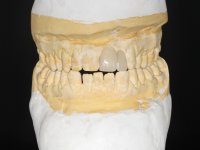

Arcade prints were made with irreversible hydrocolloid, for the lab to prepare an acrylic provisional bridge, with tooth 2.1 as abutment and tooth 2.2 as cantilever pontic. A palatal support was made to be bonded with the palatal surface of tooth 2.3. After removal of the Maryland bridge and the vestibular veneer from tooth 2.1, the dental abutment was re-prepared by making the cervical finish line intrasulcular. The provisional bridge made in the lab was relined on the mouth with self-curing acrylic and composite resin. During 6 weeks the soft tissues were worked and stabilized, preparing the consultation for impression. In this session, gingival separation was performed with kaolin paste, using the provisional bridge to compress the material into the gingival sulcus. Impression was performed using wash technique, and the provisional bridge was placed. At the end of the consultation, an impression was made from the provisional bridge placed in the mouth, using irreversible hydrocolloid. The patient had approved the aesthetics of the provisional. This information was passed on to the lab, where the work followed a silicone index, based on the shape and arrangement of the provisional bridge, approved by the patient. The cantilever bridge was built with a Zr infrastructure, with particular care in designing the connector. After being tried and approved by the patient, the prosthetic was cemented in the mouth with resin modified glass ionomer.